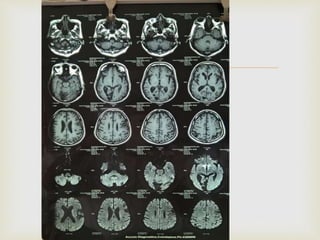

 At that time provisional diagnosis was mid brain

 The images MRI Brain showed

  At thattime provisional diagnosis was mid brain stroke.  The images MRI Brain showed